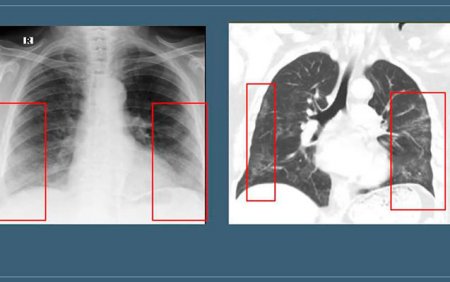

Həkim vurğulayıb ki, insanların 80-90%-ə qədəri bu xəstəliyi yüngül keçirir. Onun sözlərinə görə, temperatur 38,5-dən azdırsa, ciddi halsızlıq, boğulma, təngnəfəslik yoxdursa, KT müayinəsində ağciyərlərdə buzlu şüşə mənzərəsi 15%-dən azdırsa antibiotiklər, deksametazon qəbul etməyin, sistemlər qoşdurmayın! Bu dərmanlar orqanizmi zəiflədir. Nə qədər xəstələr bunları lazım olmadığı halda edib özlərini ağırlaşdırıblar. Baş ağrısı, boğaz qıcıqlanması, əzələ ağrıları, burun qıcıqlanması, hərarətin 38,5-ə qədər yüksəlməsi, yüngül halsızlıq, iybilmə və dadbilmə hisslərinin pozulması, yüngül öskürək xəstəliyin yüngül əlamətləridir qorxmayın. Bu yüngül əlamətlər olduqda əgər şəkərli diabet, hipertoniya, orqan transplantasiyası və yanaşı ağır xəstəliyiniz yoxdursa limon, çoxlu zoğal, moruq mürəbbəli çay, soğan-sarımsaq və indi günəş az olduğu üçün profilaktik dozada D vitamini qəbul edə bilərsiz. Yox, əgər hərarət 38,5-dən çoxdursa, boğulma, təngnəfəslik, KT müayinəsində buzlu şüşə 20% və daha çoxdursa, şəkərli diabet və ya yanaşı ağır xəstəliyiniz varsa, özbaşına müalicələr etməyin, ya təcili yardıma zəng edin, ya da covidlə məşğul olan həkimlə məsləhətləşin".